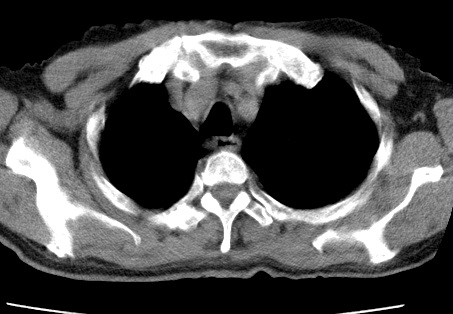

标题: CT24032:男65岁,咳嗽,吸烟20余年,无发热,咳痰 [打印本页]

标题: CT24032:男65岁,咳嗽,吸烟20余年,无发热,咳痰

考虑右肺中叶不张,请大家发表意见

右肺中叶不张、肺门轮廓增大,占位不除外;建议增强,必要时支气管镜详查。

右肺中叶支气管闭塞,中叶肺不张,右侧肺门见肿块影。中心型肺癌的可能大。建议支气管镜检查。

右中叶体积明显缩小,且其支气管未显示,先考虑:中心型肺癌班右中叶肺不张。

考虑右肺中叶中央型肺癌并右肺中叶肺不张;建议:行纤支镜检查。

右肺门旁类圆形肿块影,右肺中叶不张,建议纤支镜检查。